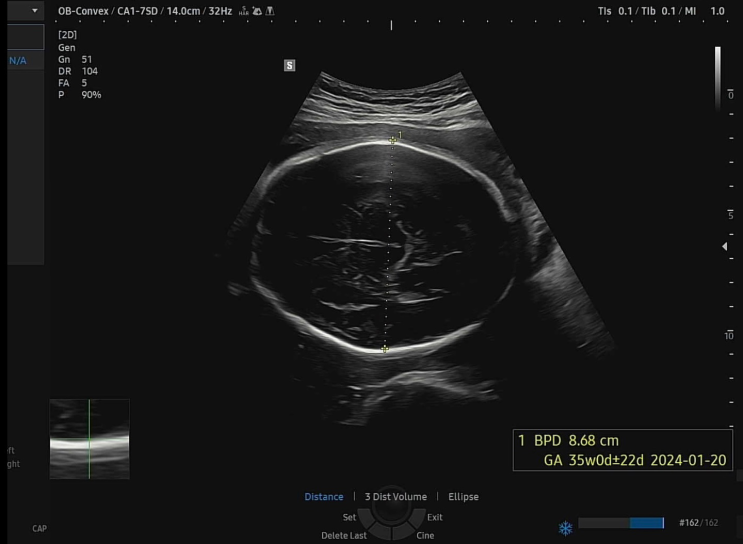

[임신일기]임신34주 - 태동검사 / 출산까지 앞으로 한 달 / 임산부 천식 치료

제왕절개로 출산방법을 정하고 나니 더더욱 얼마 남지 않은 출산...! 30여일도 남지 않았다. 이제 정말 코...